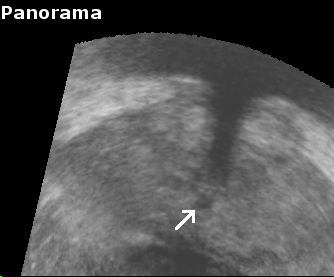

To measure reproducibility and registration success, 10 registrations were carried out for each volume pair from slightly perturbated start points by adding noise of 2mm and 2°. This yielded 10 transformations Tisubscript𝑇𝑖T_{i} that approximate the unknown rigid transformation between the prostate in both volumes. The average transformation T¯¯𝑇\overline{T} of the Tisubscript𝑇𝑖T_{i} was computed with the method presented in [9]. The euclidean distance error ϵEi=TiCT¯Csuperscriptsubscriptitalic-ϵ𝐸𝑖normsubscript𝑇𝑖𝐶¯𝑇𝐶\epsilon_{E}^{i}=||T_{i}\cdot C-\overline{T}\cdot C||, with C𝐶C being the image center, and the angular error ϵAisuperscriptsubscriptitalic-ϵ𝐴𝑖\epsilon_{A}^{i}, which corresponds to the rotation angle of Ti1T¯superscriptsubscript𝑇𝑖1¯𝑇T_{i}^{-1}\cdot\overline{T}, were used to compute the root mean square (r.m.s.) errors ϵEsubscriptitalic-ϵ𝐸\epsilon_{E} and ϵAsubscriptitalic-ϵ𝐴\epsilon_{A}. A registration was considered successful if ϵE<2.0subscriptitalic-ϵ𝐸2.0\epsilon_{E}<2.0mm and ϵA<5subscriptitalic-ϵ𝐴5\epsilon_{A}<5 degrees, and if the result T¯¯𝑇\overline{T} was visually satisfactory when superimposing both volumes in a composite image (See Fig. 2).

Reconstruction accuracy evaluation was more difficult to implement since there is no straight-forward gold standard. In some images, the needle trajectories from previous biopsies were still visible. In these cases, the trajectories were manually segmented, and the angular error between corresponding needle trajectories were used to evaluate rotational accuracy. Also, some patients had significant and clearly visible calcifications inside the prostate. The distances between segmented calcifications were used to determine the translational accuracy. Tab. 1 and Fig. 2 show the results of the evaluations.

Figure 2: Registration accuracy: (a) shows the target image, and (b) the aligned panorama image. In (c) both volumes are superimposed to illustrate registration accuracy for the urethra (arrow), and (d) illustrates the registration accuracy in the upper gland.